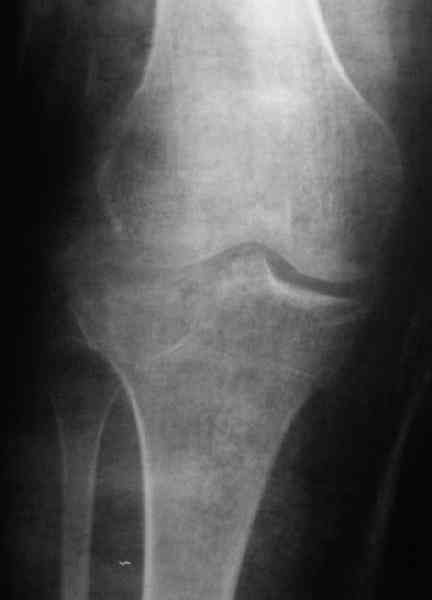

Re: Застарелый перелом 41С3

Дорогой коллега, застарелых переломов, во первых, не бывает. Они бывают сросшиеся, не сросшиеся и т.п. Во вторых, эндопротезирование на данном этапе технически очень затруднительно. Я бы предложил два варианта, первый - это консервативное лечение, с разгрузкой сустава, ортезированием и лечебными блокадами или второй - оперативный - ЧКДО аппаратом Илизарова на бедро - голень, растянуть сустав, попытаться, если перелом еще не консолидировался, исправить ось. Во всяком случае, на фоне дистракции легче провести разработку движений.

По тактике лечения, более импонирует второй вариант, но наружная плато расколота и туда при нагрузке внедряется н/мышелка бедра, поэтому после дистракции как репонирвать: или стяжными винтами, или изогнутами спицами или субхондральная костная пластика?